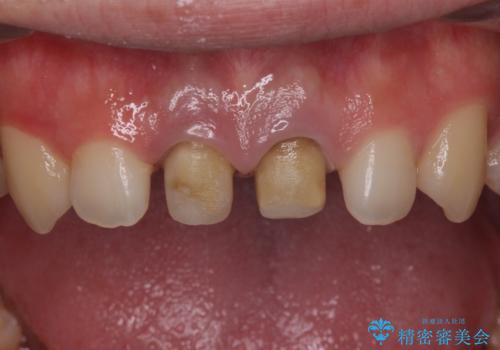

二本とも神経の治療のやり直し(再治療)を行ってからセラミックを入れています。

- 52.8万円 セラミッククラウン(メタルボンドクラウン11万円×2 仮歯1万円×2 ファイバーコア2万円×2 再根管治療9万円×2)費用は治療当時の料金となります

今回は、前歯のかみ合わせが深く、下の前歯が根元にかみこむような状態だったため、オールセラミックは難しく、メタルボンドクラウン(金属の裏打ちにセラミックが盛ってあるクラウン)となりました。

神経の治療をした歯は変色してくるため、歯ぐきから歯の根が透けて見えるのは治療はむずかしいです。